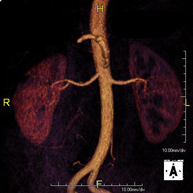

- Abdominal aorta MRI angiography

A non-invasive diagnostic test that involves studying the abdominal aorta, obtaining high-definition anatomical images using an electromagnetic field and radio waves (with transmitter and receiver). The use of paramagnetic contrast (gadolinium) is essential. However, it is a radiation-free procedure. The quality of the images allows for 2D and 3D reconstructions. It is indicated in patients with vascular disease (atherosclerosis), aneurysm studies, pre-surgical studies of lesions adjacent to the abdominal aorta as a vascular ‘map’, etc.

A non-invasive diagnostic test that involves studying the abdominal aorta, obtaining high-definition anatomical images using an electromagnetic field and radio waves (with transmitter and receiver). The use of paramagnetic intravenous contrast (gadolinium) is essential. However, it is a radiation-free procedure. The quality of the images allows for 2D and 3D reconstructions. It is indicated in patients with vascular disease (atherosclerosis), aneurysm studies, pre-surgical studies of lesions adjacent to the abdominal aorta as a vascular ‘map’, etc.